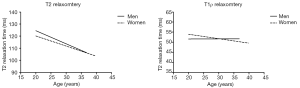

Figure 4 shows a graphical representation of the relationship between the relaxation times obtained by relaxometry maps and the subject characteristics. There was a negative correlation between age and T2 relaxation time (r=−0.30, P<0.0001) and a positive correlation between disc volume and relaxation time T2 (r=0.15, P=0.002) (Table 3).

As shown in Table 4, we observed a negative linear correlation between T2 relaxation times and age at all lumbar disc levels (P<0.02 at all levels). There was no correlation between age and volumetry for any disc (P>0.07 at all levels). We also observed no relationship between age and T1ρ values for any disc level (P>0.06 at all levels). BMI, height and weight were not correlated with any lumbar IVD relaxometry measurement.

Figure 5 is a graphical representation of the T1ρ and T2 discs relaxation times for men and women according to the age. In relaxometry T2 it is possible to perceive a decay in values with aging in men (r=−0.43, P=0.004) and women (r=−0.41, P=0.003). This decrease is slightly more pronounced in men (curve slope =−1.08±0.35) than in women (curve slope =−0.83±0.27).